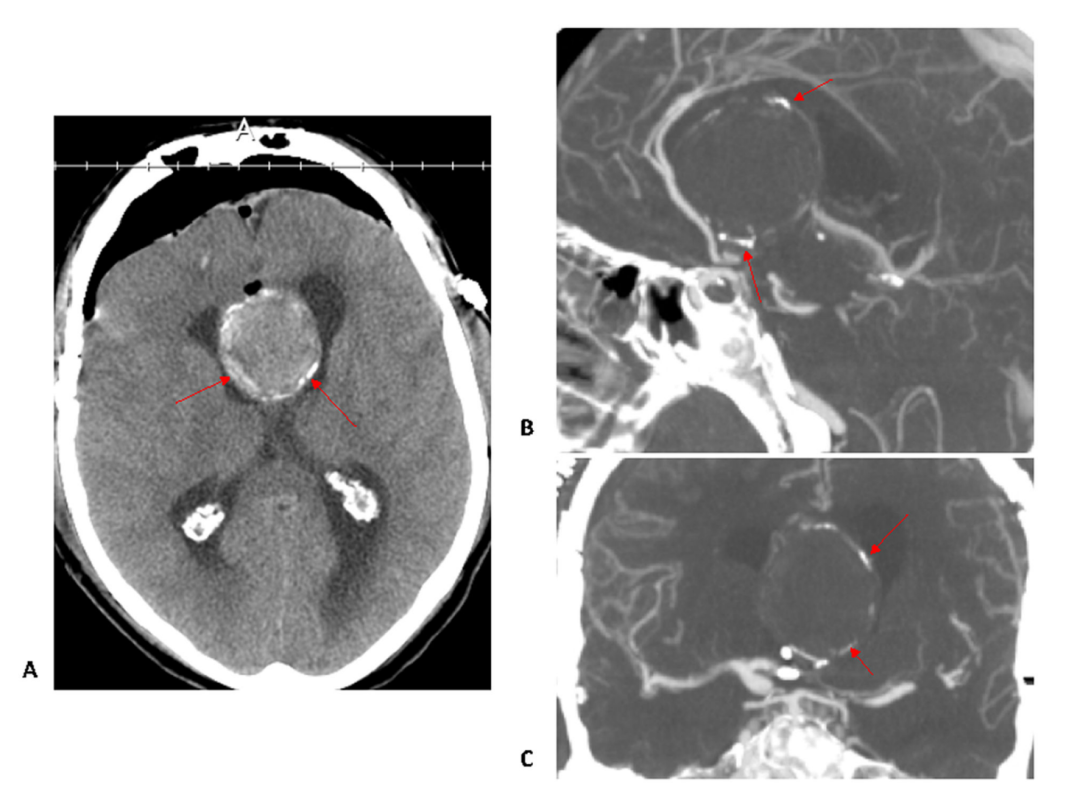

巨大前交通动脉瘤伴瘤颈及同心圆钙化

这是一例经开颅术治疗的伴瘤颈及同心圆钙化的巨大前交通动脉瘤例子(红色箭头)。

影像学表现:

- A) 轴位平扫CT:清晰显示同心圆状钙化结构

- B) 矢状位CTA:瘤颈处明显钙化、瘤周薄层钙化环、A2段血管前移变形征象

- C) 冠状位CTA:典型蛋壳样钙化(瘤壁弧形薄层高密度影)

由于瘤颈及瘤体呈现同心圆状钙化(红色箭头所示),常规动脉瘤夹闭术难以实施。最终采取复合手术方案:

- 1)近端A1段动脉瘤夹闭

- 2)A3-A3侧侧吻合搭桥

- 3)右侧M2-A2桡动脉移植搭桥

本案例诠释了钙化病变对神经外科术式选择的决定性影响,需结合三维影像评估制定个体化方案。